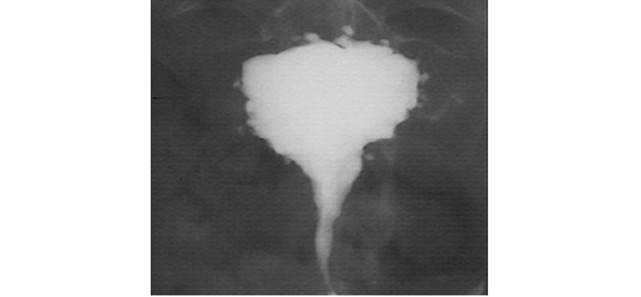

Больная Б., 36 лет, обратилась к врачу женской консультации с жалобами на обильные, болезненные менструации, периодические запоры

В л а г а л и щ н о е и с с л е д о в а н и е: наружные половые органы развиты правильно. Влагалище — не рожавшей женщины. Шейка; матки субконической формы, чистая. Матка увеличена до 12 нед. беременности, плотная, подвижная, безболезненная. При­датки с обеих сторон не определяются, область их безболезненна. Выделения кровяные, обильные.

Проведено обследование. Данные гистерографии представлены на рисунке.

Поставьте диагноз.

гистерография:

поликистоз; //

рак яичников; //

аномалия матки; //

тубовариальное образование; //

+множественная субсерозная миома матки